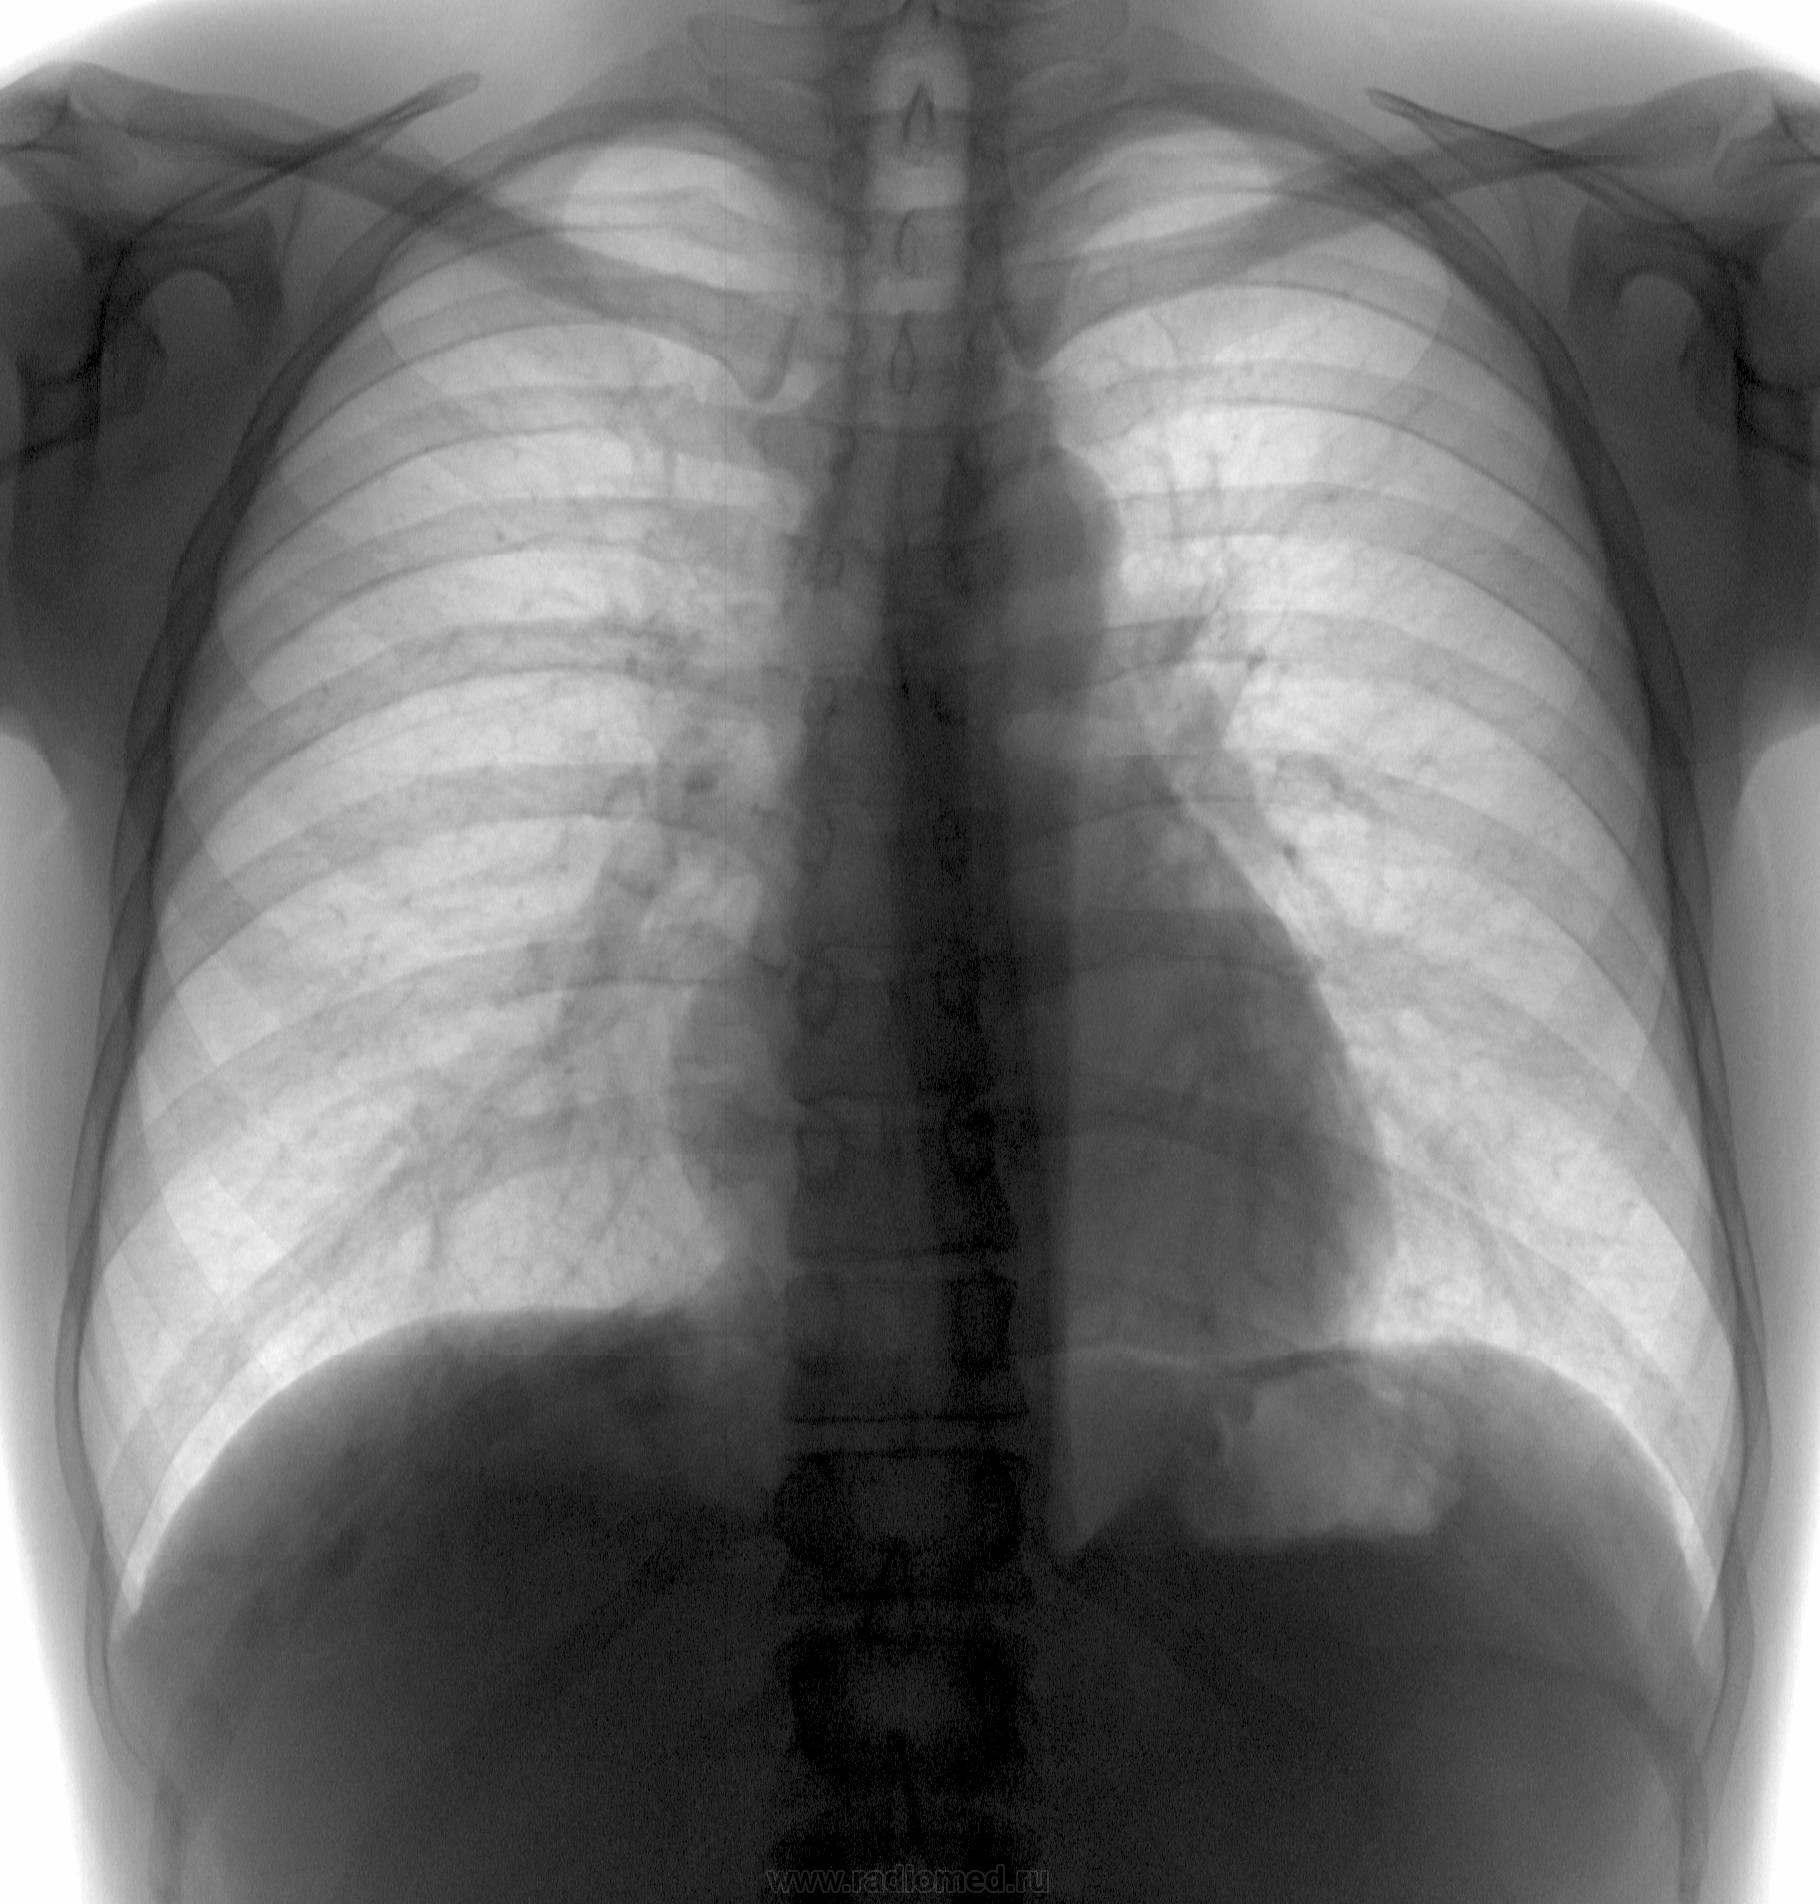

Шаровидная тень: в S4 в/доли слева (1 случай) и S10 н/доли справа (2 случай)

Татьяна Валентиновна, асолютно согласен. что основной рентгенологический признак - шаровидные тенеобразования, но...достаточно ли они "шаровидны" и достаточно ли однородны....+молодой, в общем то возраст, + отсутствие существенных жалоб. Конечно, смущает тот факт, что это не первые их ФГ (но у меня то они впервыеwink). Опять же - в С10 (скрывается за тенью печени), в С4 слева (не факт, что раньше было перекрыто левым краем сердца) и, как следствие - не были обнаружены.

Внутрилегочная секвестрация или артериовенозная мальформация.

Она самая))). Да, оба случая подтверждены на КТ.

Нечего сказать. Вспомнился мой же №5'). из вопросной ветки... С одной стороны патология видна и на обзорных (в обоих случаях). С другой - с учётом отсутствия жалоб, клиники диф. ряд получился бы немалым. Приоритет диагностики в отношении а/в мальформаций, конечно, у КТ/МСКТ, но гарантирую, что во втором случае с парнем поставил бы (если бы не забыл по такой Rg-картине) эту нозологию далеко не в первых числах...

Со вторым парнем я тоже растерялся...и просто тупо назначил контрольную КТ, и вот надо же было так совпасть, что явились они оба в один день, и парень - на контроль с данными КТ , и барышня - на первичное обследование. Сначала я выставил барышне подозрение на мальформацию и отправил ее на КТ, почти сразу же после нее пришел парень, где выяснилось и его состояние. Данные по барышне поступили на следующее утро. Вот такая история. А заодно - и "закон парных случаев". Так что сработал я самостоятельно - только на 50%, хорошо, что хоть ничего не пропустил по прямому (это к вашим постам по поводу рентгенографии в одной проекции и пользы от цифровой ФГ).